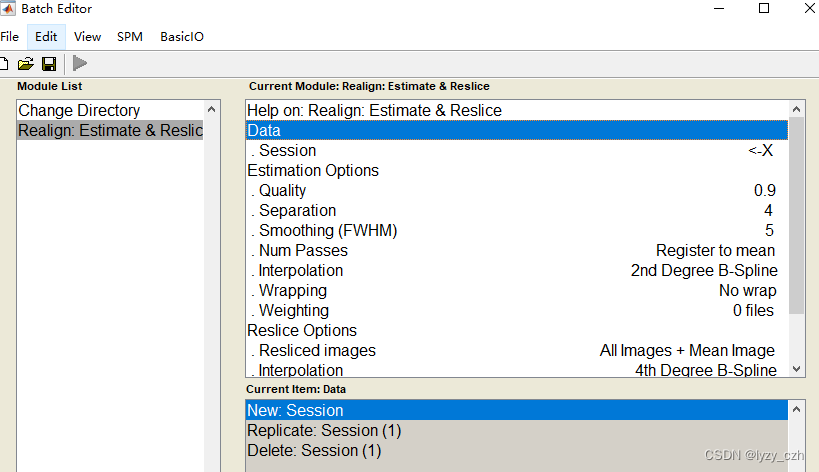

6)最后一步进行8mm的平滑

依次选择所有步骤如下一共5个步骤:

注意在Image Calculator的Expression输入是固定的因此可以直接在这里输入如下: